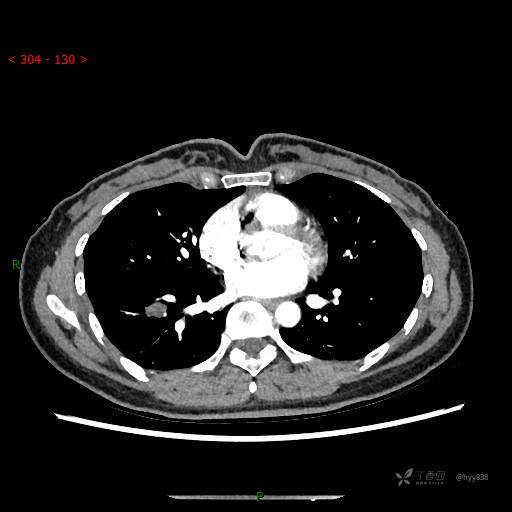

静脉期

CT值